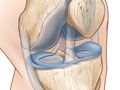

La resonancia magnética es una prueba que se realiza con una máquina de gran tamaño que utiliza un campo magnético e impulsos de energía de ondas de radio para obtener imágenes de la rodilla. Los músculos, ligamentos, cartílagos y otras estructuras articulares suelen verse mejor con una resonancia magnética. En muchos casos, una resonancia magnética proporciona información sobre estructuras del cuerpo que no pueden verse tan bien con una radiografía, una ecografía ni una tomografía computarizada.

• Encontrar problemas en la articulación de la rodilla, como artritis, tumores óseos o infección, o cartílagos, meniscos, ligamentos o tendones dañados.